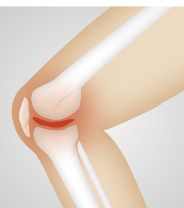

무릎 관절에 좋은 음식 무릎 관절 관리 방법 등 정보에 대해 알아보도록 하겠습니다. 무릎 관절은 우리 몸에서 가장 중요한 부위 중 하나입니다. 다리를 지탱하고, 움직임을 제공하는 기능을 수행합니다. 무릎 관절은 대개 체중과 운동에 의해 과부하가 걸리기 때문에, 연령과 상관없이 다양한 질환과 손상이 발생하기 쉽습니다. 무릎 관절 질환에는 퇴행성 관절염, 무릎 관절염, 슬관절 연골손상 등이 있습니다. 이러한 질환은 무릎 관절 통증, 붓기, 운동 제한 등의 증상을 유발합니다. 무릎 관절 건강을 유지하기 위해서는 적절한 운동, 올바른 식습관, 적절한 체중 유지, 적절한 자세 등이 필요합니다. 무릎 관절 질환의 예방과 관리를 위해서는 정기적인 건강 검진과 치료가 필요합니다.

무릎 관절염 증상

무릎 관절염의 증상은 다음과 같습니다.

- 통증: 무릎 관절염의 가장 일반적인 증상은 무릎 주변의 통증입니다. 특히, 오랫동안 앉거나 서 있거나 움직일 때 더 심해집니다.

- 뻣뻣함: 무릎 관절염은 무릎 관절의 뻣뻣함을 유발합니다. 무릎 관절의 움직임이 제한되며, 일어나거나 앉는 것이 어려울 수 있습니다.

- 부종: 무릎 관절염으로 인해 무릎 주변의 부종이 발생할 수 있습니다. 부종은 무릎 관절에 더 많은 압력을 가해 더 많은 통증을 유발합니다.

- 열감: 무릎 관절염은 관절 주위 조직의 염증으로 인해 무릎 주변에서 열감을 느낄 수 있습니다.

- 소리: 무릎 관절염은 무릎 관절에서 윤활제 분비 감소로 인해 뼈가 마찰되어 생기는 부적합한 소리를 유발할 수 있습니다.

무릎 관절염의 증상은 진행되는 정도에 따라 다양합니다. 초기에는 가벼운 통증이 있을 수 있으나, 진행되면서 무릎 관절의 기능 저하와 더 심한 통증이 발생할 수 있습니다. 무릎 관절염이 의심되면, 증상이 심화되기 전에 적극적인 치료와 예방 조치를 취하여 증상의 악화를 방지해야 합니다.